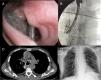

We report the case of a 54-year-old male diagnosed in November 2018 with esophageal cancer with mediastinal involvement and histology consistent with epidermoid carcinoma. The mass caused esophageal stenosis, manifested clinically as difficulty swallowing liquids, excessive salivation, and aspiration pneumonia in the right lower lobe. A 32 × 210 mm self-expanding metal esophageal stent (SEMS) was placed (subsequently replaced due to intolerance with a 23 × 105 mm Wallflex® Fully Covered SEMS, Boston Scientific®) and an 35 mm Amplatzer® atrial septal defect occluder (Abbott®) was inserted due to loss of integrity of the distal third of the tracheal posterior wall. Given the lack of resolution of the clinical picture, flexible bronchoscopy was performed, which confirmed the presence of a large tracheal defect, with visualization of both previously implanted devices (Fig. 1A). An Aerstent® tracheal Y-stent with partial polyurethane coating (Leufen®) measuring 40 × 20 × 30 mm was implanted using fluoroscopy-guided rigid bronchoscopy without complications. Additional intra- and post-operative imaging tests showed correct positioning of the 3 devices (Fig. 1B, C, and D), while the patient’s clinical situation improved.

A) Flexible bronchoscopy view showing a continuity defect in the posterior wall of the distal third of the trachea, with visualization of esophageal stents and atrial septal defect occluder. B) Fluoroscopic view of the 3 normally positioned stents by flexible bronchoscopy through rigid bronchoscope. C) Chest CT image without intravenous contrast, axial plane, lung window showing the presence of the 3 devices used for closing the fistula. D) Plain post-anterior chest X-ray after intervention showing correct positioning of the 3 implanted devices.